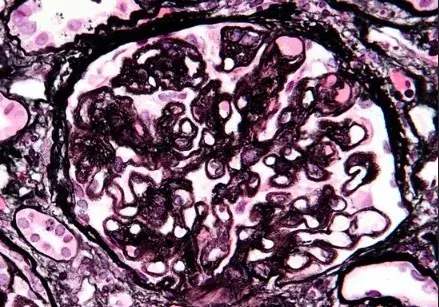

nefrite lupica